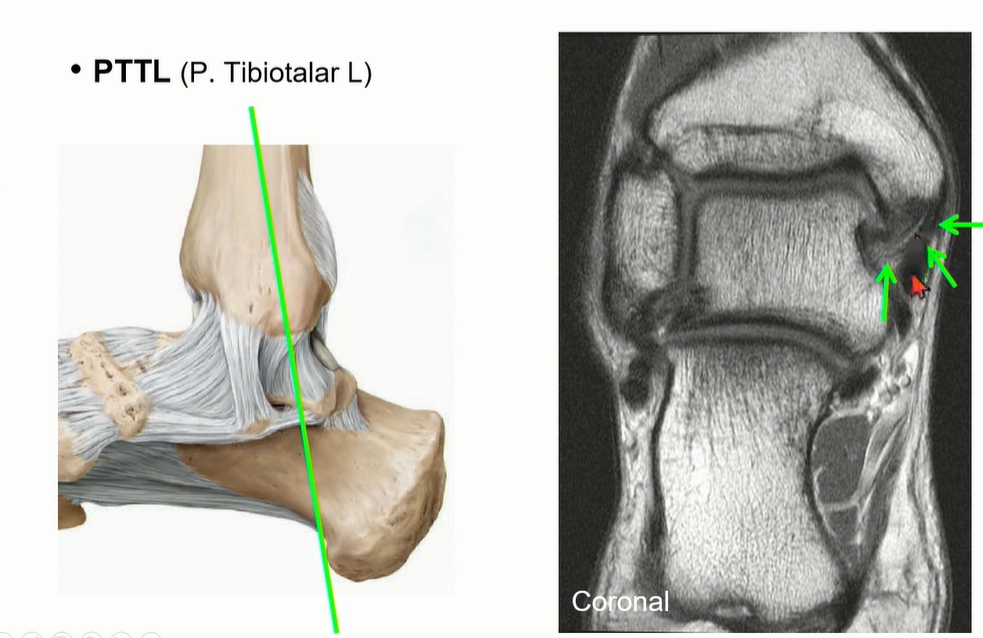

Deep deltoid liagment의 하나인 PTTL의 주행.

ATTL에 비해서 넓어서 영상에서 확인이 용이하다. ligament 사이에 fat이 관찰되는 것이 정상.

coronal cut에서도 fat때문에 straiation이 보이는 것이 정상이다.